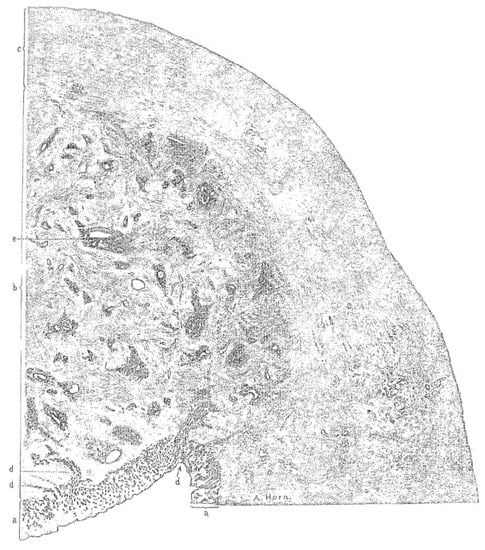

3.1. Histopathology